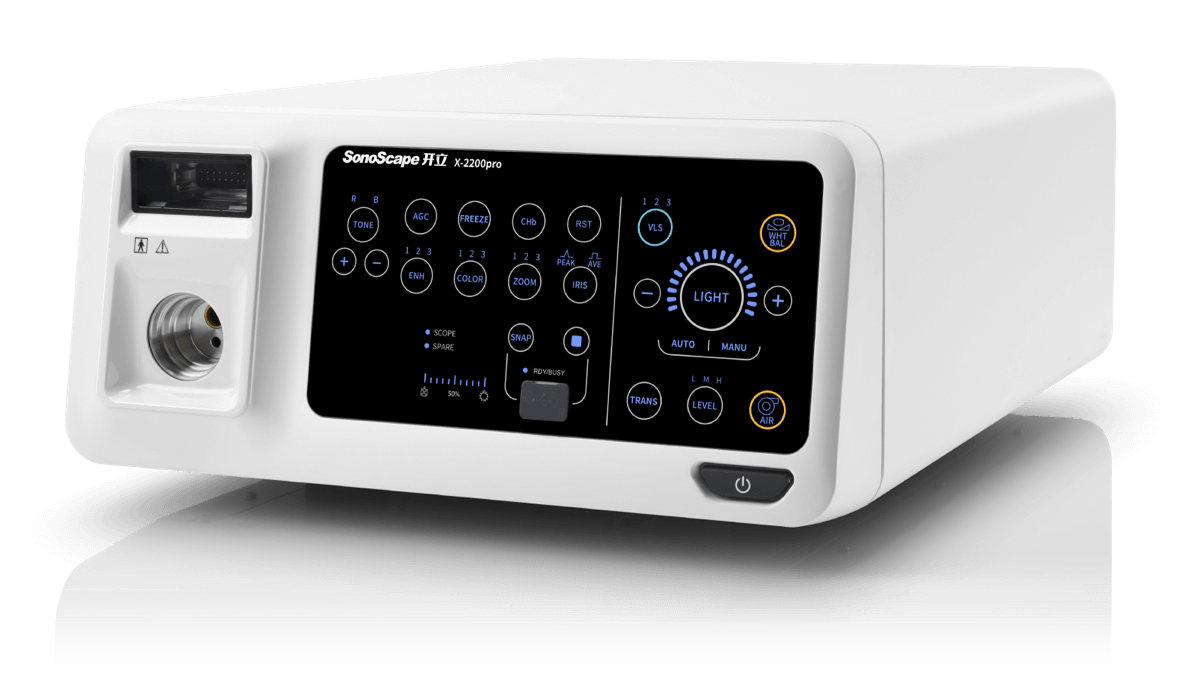

X-2200pro

高清电子内镜系统

高清电子内镜系统

百万级像素传感器,1080P视频信号输出,图像清晰

具有聚谱成像技术(SFI)及光电复合染色成像技术(VIST) 能够呈现粘膜细节及病变特征

多种光谱组合,光源平均使用寿命≥50,000小时,低功耗等可减少科室运行成本